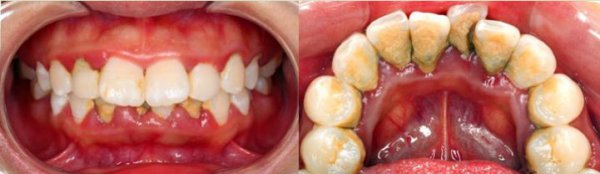

牙齿上结满牙结石,还长满了绿色的“苔藓”,而这“苔藓”是细菌长期在牙齿上繁殖出来的菌斑,就像过期的食物不处理掉,就会长霉斑一样。

牙菌斑的堆积会刺激牙龈,引起牙龈炎症,牙龈就会变成鲜红色或者暗红色,质地松软,容易出血,特别是刷牙或者咬硬物时容易出血,还会有口臭。而且小吴的牙龈炎症已经影响到牙根周围的牙槽骨,牙槽骨有炎症会导致骨头吸收,就像树根周围的水土流失,而导致牙齿松动。